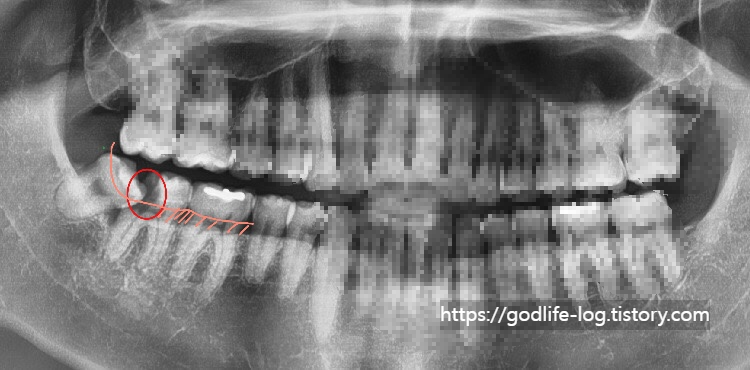

위 사진 또한 사랑니 때문에 어금니에 충치가 생긴 모습인데요, 분홍색 선으로 표시해 놓은 곳이 실제 우리 눈에 보이는 잇몸 부분이고 아래쪽으로는 잇몸에 덮여있어서 보이지 않는 곳입니다. 충치가 잇몸 안쪽에 안 보이는 부분까지 깊이 생겨서 이런 경우에는 사랑니를 발치한다고 해도 어금니를 충치치료해서 살리기가 어렵습니다